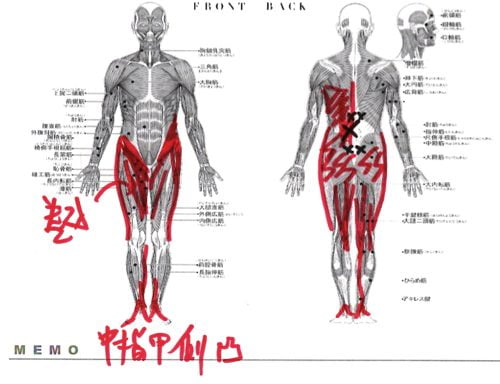

お身体の状態を診させて頂くとこんな状態でした。

赤い線は筋肉や腱の硬直やヨジレ

Xは痛みの部分

背中側を診てみると丁度こんな感じで

腰の上と下の筋肉や腱が硬直して引っ張っている状態

上下から引っ張られる状態で余裕のなくなった腰は

少し前かがみになると張り詰めてしまい激痛を生み出します。